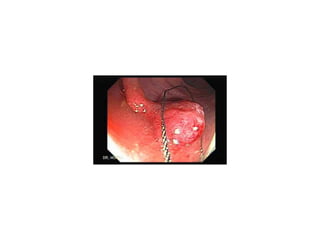

Pólipos Colon Hasta un 97% de los CCR se inician a partir de un  pólipo adenomatoso, considerandose una lesión pre-maligna. Un pólipo es una masa aislada de tejido que crece hacia la luz intestinal.  La mayoría de los pólipos no producen síntomas

Pólipos colónicos Habitualmente  no causan síntomas . La  colonoscopia  es el mejor método para detecta pólipos y permite resecar la mayoría de los pólipos durante la exploración sean hiperplásicos o adenomatosos.

Cribado Pruebas de Detección Temprana Colonoscopia Se realiza cuando la prueba de sangre oculta en heces es positiva. Con correcta limpieza del colon. Si se encuentra algún pólipo, éste puede ser extirpado al mismo tiempo.